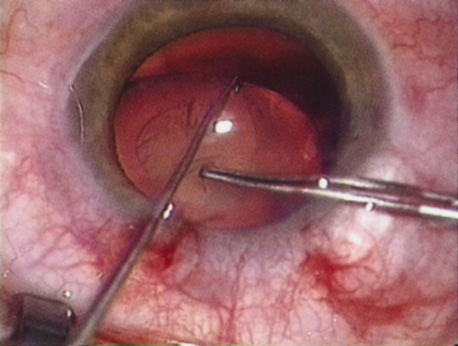

Patients who complain of glare from point sources of light, such as oncoming headlights or bright sunshine, may be best evaluated by a different form of glare testing. To simulate the environment of the patients' symptoms, Snellen acuity is measured while directing a point source of light obliquely toward the eye outside their best spectacle correction or outside of a phoropter dialed in with their best manifest refraction (Fig. 2).